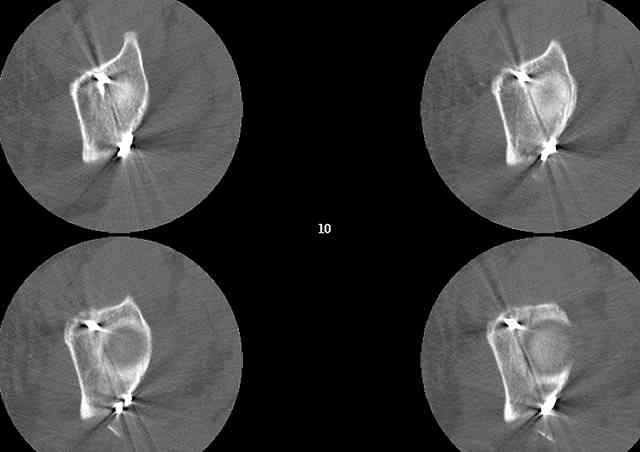

A CT scan will rarely lie to you...reveals your reduction and implants...we use it to assess, teach, grade, and try to get better next time.